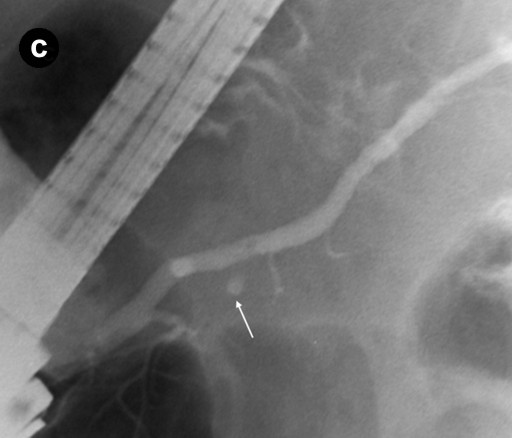

The patient remained clinically stable for 3 years without any overt gastrointestinal or constitutional symptoms. Because the CA 19-9 continued to fluctuate, and because of the patient’s concerns that the pancreatic cysts may become malignant, a very rigorous surveillance program was carried out with two ERCPs (2003 and 2004), three EUSs (2003, 2004, and 2006), three CTs (2003, 2004, and 2006) and five MRCPs (2003, 2004, 2005, 2006, and 2008) (Figure 3). The main pancreatic duct was not dilated on any of the examinations. The subcentimeter cyst was present in the head of the pancreas, which were unchanged compared to imaging studies from 2003 to 2008. However, in 2009, an MRCP revealed a 2 cm solid mass in the pancreatic head, adjacent to the cyst and compressing common bile and pancreatic ducts (Figure 4). Immunochemical findings of the fine-needle aspiration (FNA) specimen were diagnostic for ductal adenocarcinoma (Figure 5). Because of unresolving Lady Windermere syndrome, patient age, and patient preference, chemotherapy would be more appropriate than surgery. The patient received one cycle of gemcitabine and developed respiratory distress with atrial fibrillation, resulting in prolonged hospitalization. Eventually, the patient expired from respiratory failure.

Figure 3. CA 19-9 level and different imaging modalities during follow-up of "low-risk" branch-duct IPMN. Lady Windermere syndrome and "low-risk" branch-duct IPMN are both associated with raised CA 19-9. We suspected elevated CA 19-9 level was secondary to both disease processes. Arrow legend: yellow: EUS (n=3); green: ERCP (n=2); purple: pancreatic CT protocol (n=3); blue: MRCP (n=5). |